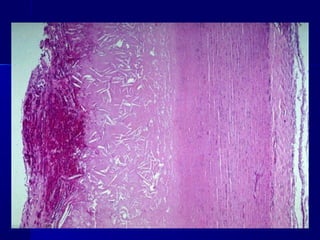

Amiloidosis (hialinización) de un islote del páncreas de un paciente

con diabetes mellitus de tipo 2

Amiloidosis (hialinización) deun islote del páncreas de un paciente con diabetes mellitus de tipo 2